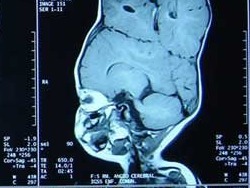

SLA Biomodel® of Cerebral Arterio-venous Malformation and surrounding skull, data from a CT Angiogram. Allows advanced neurosurgical planning. (Ref: Anatomics Pty. Ltd. www.anatomics.net)

Sağda: Beyine ait yumuşak doku tomografi verisine bağlı olarak inşa edilmiş ve değişik renklerde modellenmiş. Bu sayede gelişmiş bir beyin ameliyatı planlaması yapılabilir.